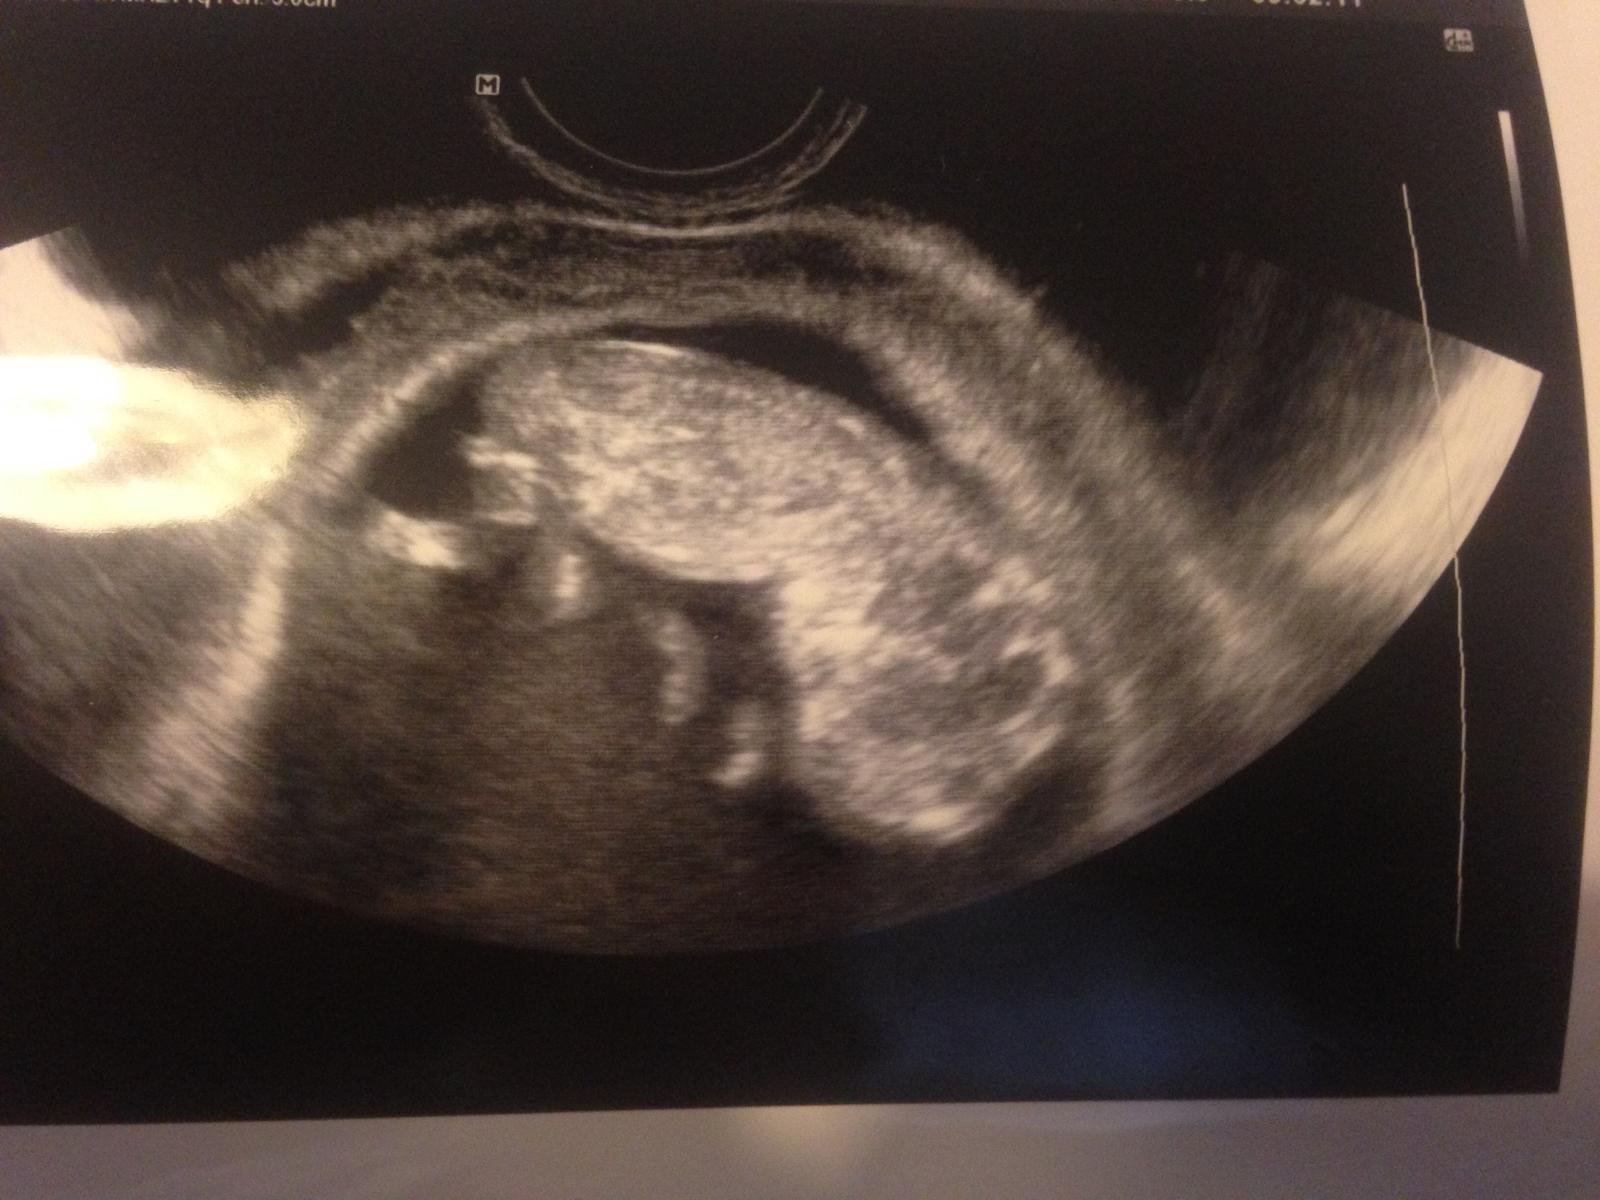

Ahojte zienky potrebujem pozitivnu energiu pred dvoma dnami sme boli na poradni a dopadla na jednotku drobcek bol nadherny hral sa s prstekmi aj nam zakyval ... No vsak moj problem je ze v 6tt sa mi objavilo spinenie utekali sme na pohotovost dali mi ascorutin a povedali ze vsetko je v poriadku dnes koncime 12tt a objavilo sa mi mierne spinenie opat hrozne som sa zlakla ☹ nemam ziadne velke bolesti ani nic ☹ pisala som aj svojmu lekarovi a on ze sa nemam bat ze mam pockat a ak by sa to zhorsilo mame ist na pohotovost.. Docitala som sa ze krcok je v tehu viac prekrveny a mozu popraskat cievky .. Ako je pravda ze vysetrenie bolo trochu neprijemne pre mna ale zase zeby sa to objavilo o 2 dni ? Pridavam aj fotecku nasho drobceka ..

@michaella17 Neboj sa a ver, ze drobcek je a bude v poriadku a ze vsetko sa bude vyvijat ako sa ma...To spinenie urcite mava viac zien v tehu a vtedy jedine co viem ze treba urobit, je vylozit si nohy hore a vela oddychovat, nech to ustane...Urcite Ti tu napisu zienky, ktore daco podobne prezili a maju nadalej zdrave tehulkovanie alebo uz dokonca porodili zdrave babätka...Velmi na vas myslim a prosim Ta, ver svojmu babätku a skus byt v klude...Stres a obavy nerobia dobre ani Tebe a ani jemu...Prajem Ti krasny den a pohladkaj za mna brusenko 🤰❤😘...Inak krasna fotecka zo sona 😀